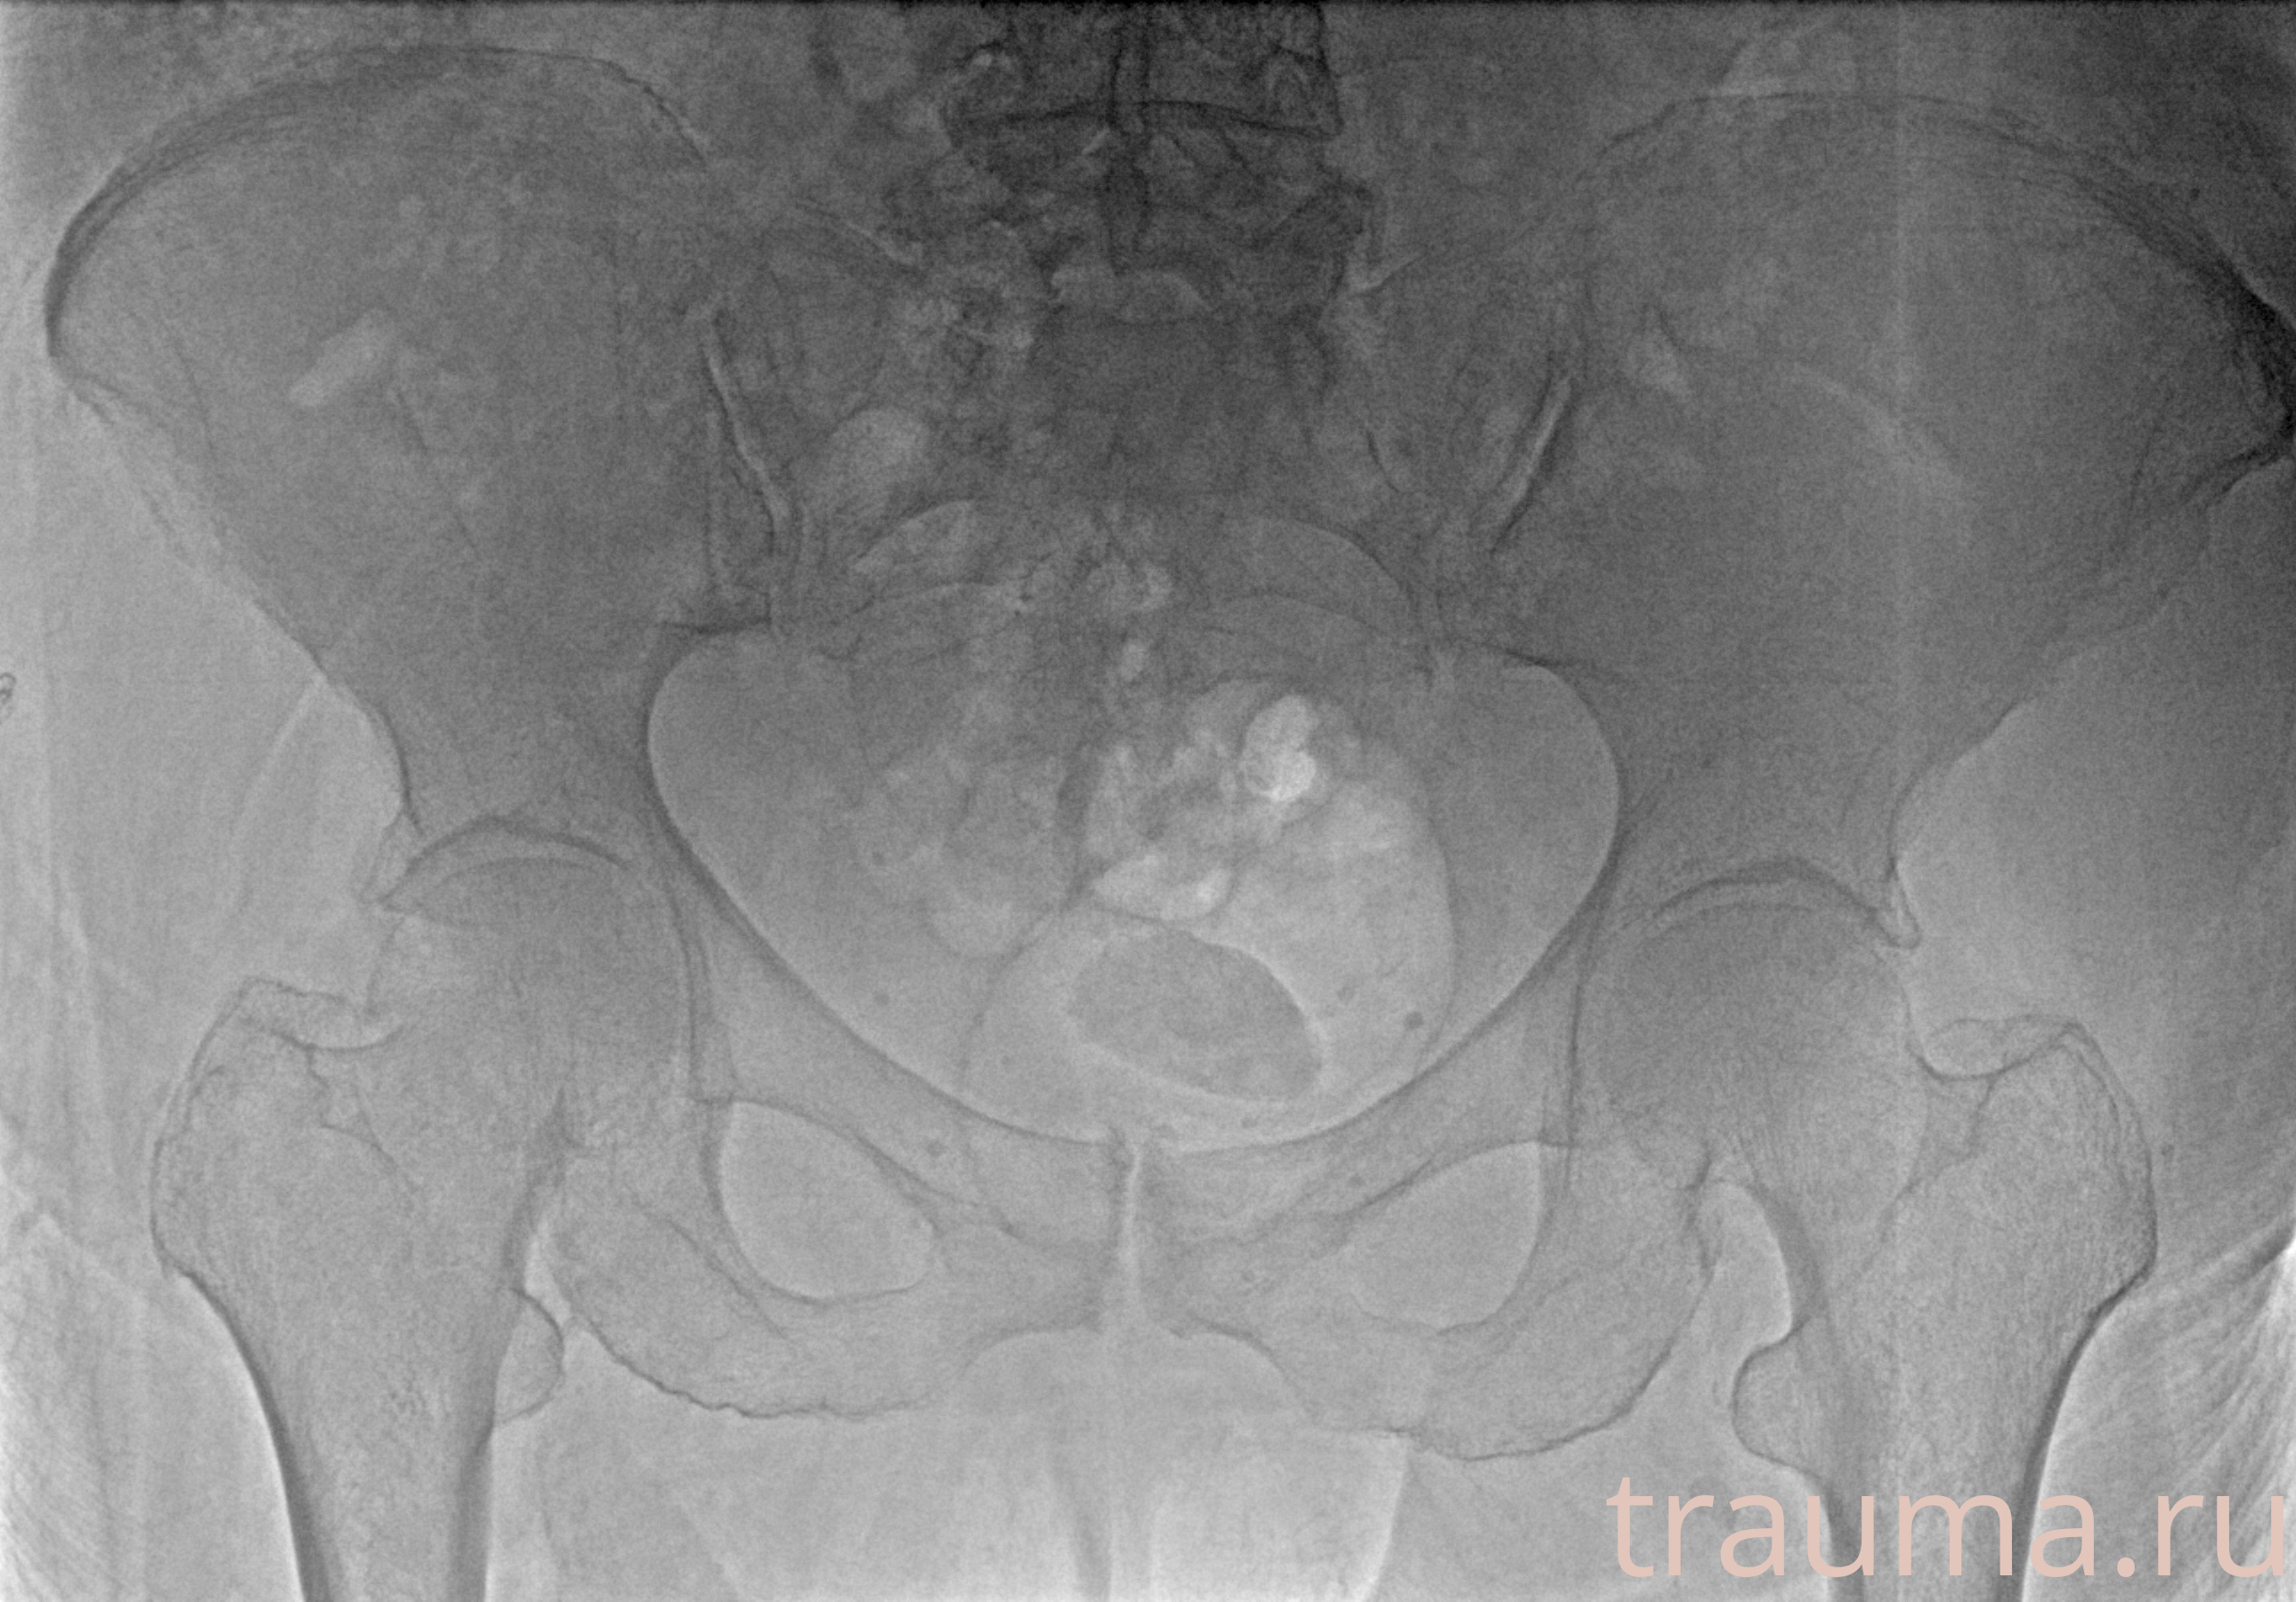

Рентгенограммы

Рентген на дому: по вашему адресу приезжает врач-рентгенолог, травматолог-ортопед с мобильным рентгеновским аппаратом, проводит диагностику травмы или заболевания, делает необходимые рентгенограммы, дает рекомендации по дальнейшему лечению. Получить качественные снимки в домашних условиях возможно благодаря уникальной методике, разработанной МосРентген Центром для института  Склифосовского